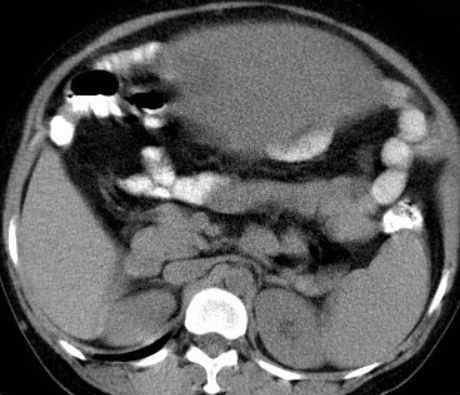

病史:女,51岁。没有任何不适,家人以为他们胖了。

病理结果:浆膜下子宫肌瘤(阔韧带肌瘤)

术中发现与左侧子宫壁、阔韧带关系密切,与左侧卵巢有粘连。

影像表现:

2.CT检查

大部分都是偶然发现的。子宫呈骨状,或子宫局部增厚,与子宫肌密度一致。变性时密度低,钙化时密度高。增强程度弱于子宫肌。

此例为巨大阔韧带肌瘤,易于诊断。